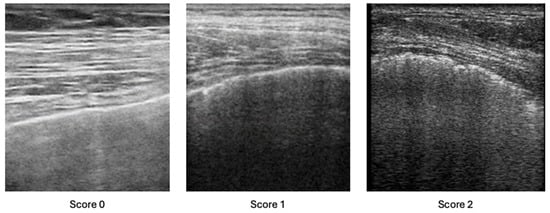

2.2. Lung Ultrasound Assessment